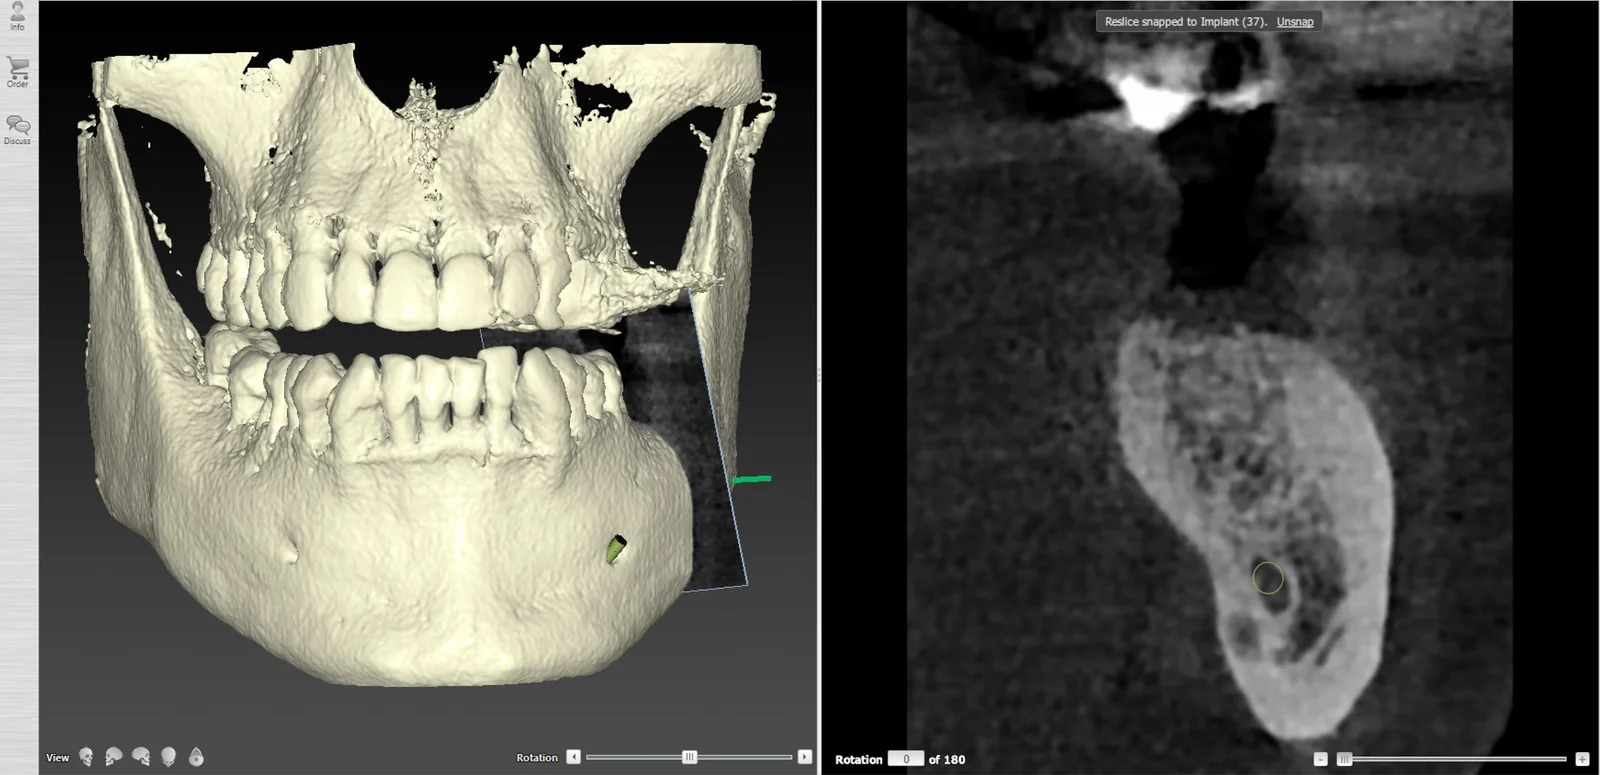

Un Cone Beam 3D est systématiquement réalisé pour analyser avec précision la quantité et la qualité osseuse disponible au site implantaire, ainsi que pour repérer les structures anatomiques à respecter (nerf alvéolaire inférieur, sinus maxillaire, etc.).

L’ensemble de ces données permet ensuite de réaliser une planification implantaire précise, fondée sur une analyse tridimensionnelle croisée des tissus durs et mous, et tenant compte des exigences prothétiques.

À partir des données recueillies lors de la première consultation ( Cone Beam 3D, empreinte optique, examen clinique et anamnèse médicale ) une planification implantaire tridimensionnelle est réalisée à l’aide de logiciels spécialisés.

- Positionner virtuellement l’implant de manière idéale, en respectant à la fois les contraintes anatomiques (canal mandibulaire, sinus, racines adjacentes, structures nerveuses) et les contraintes prothétiques (axe d’émergence, espace disponible, équilibre occlusal, esthétique) ;